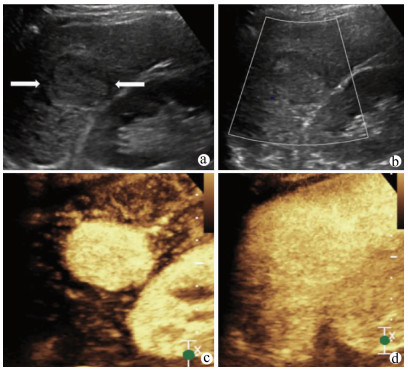

肝病超声诊断指南

中华医学会超声医学分会, 中国研究型医院学会肿瘤介入专业委员会, 国家卫生和健康委员会能力建设和继续教育中心超声医学专家委员会

2021, 37(8): 1770-1785. DOI: 10.3969/j.issn.1001-5256.2021.08.007

摘要(3138) HTML (6640) PDF (9311KB)(810)

超声检查无创、实时、价廉,无辐射、便于反复进行,是最常用的肝脏影像学检查方法。近年来,超声检查新技术如超声造影、弹性成像发展迅速,可有效鉴别肝内占位性病变性质、评估肝纤维化和门静脉高压程度以及监测肝病治疗效果,在临床肝病及其介入治疗中发挥重要诊断价值。本指南规范了肝病多模态超声技术(灰阶超声、彩色多普勒超声、超声造影、弹性超声)检查的仪器调置、患者准备及医生检查方法;对肝脏弥漫性病变(炎性病变、纤维化、硬化)、多种占位性病变及肝病介入操作的多模态超声技术诊断标准进行了定义和规范,同时推荐了超声监测周期及肝脏疾病超声诊断报告书写规范。